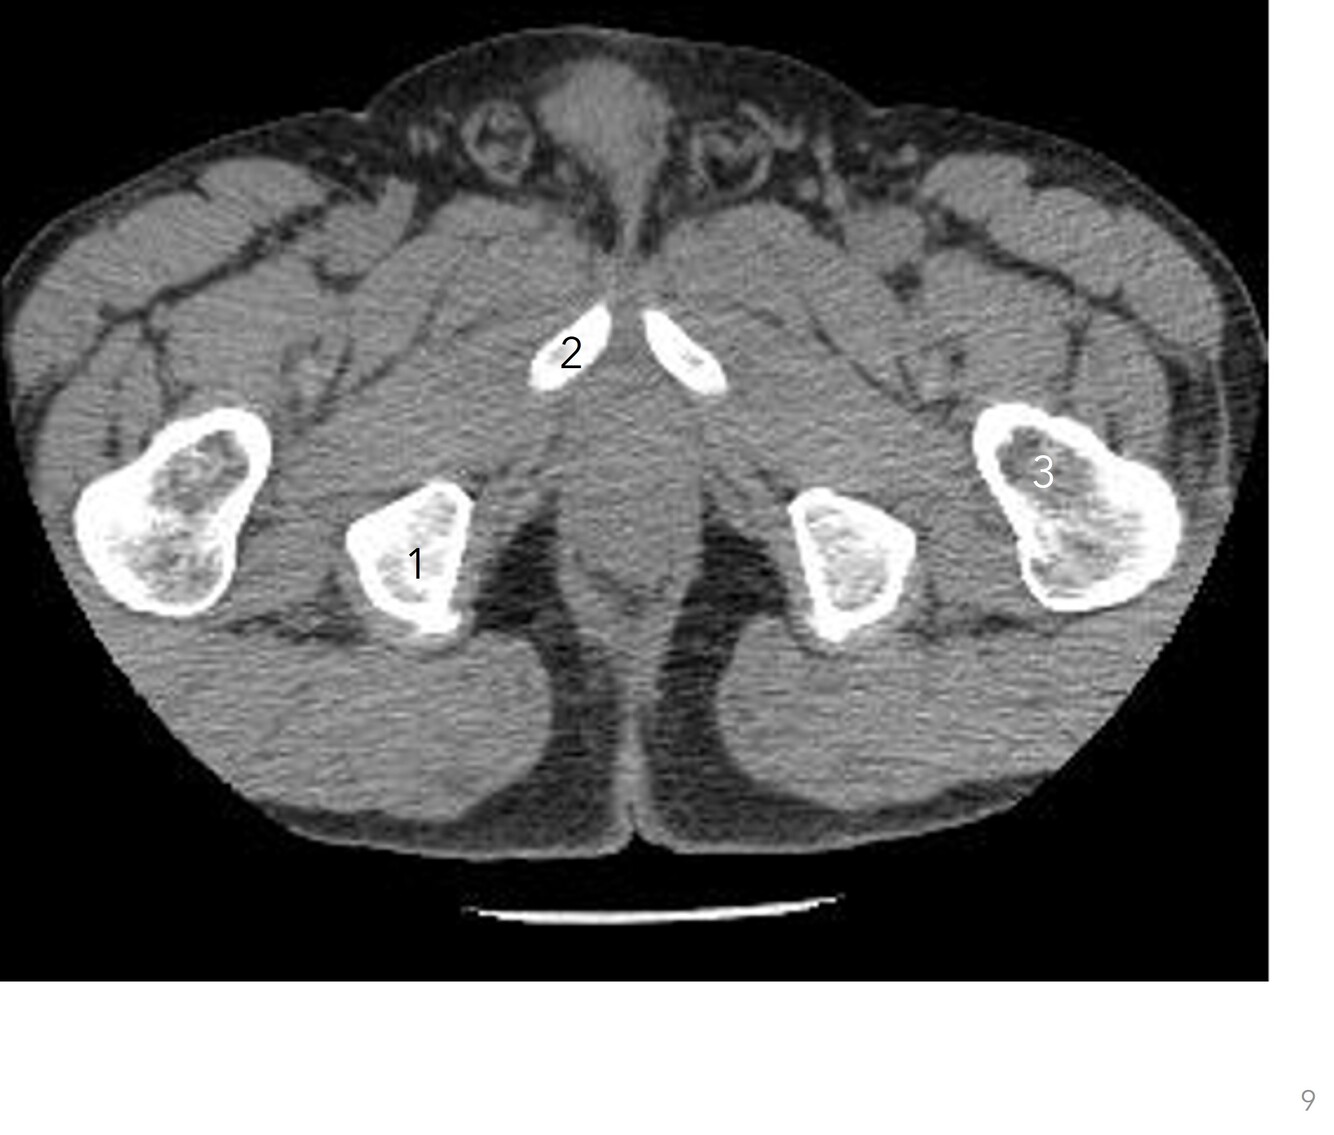

8

Q

Label 1-3

A

1. Rt superior ischial ramus

2. Rt inferior pubis ramus

3. Lt femoral neck